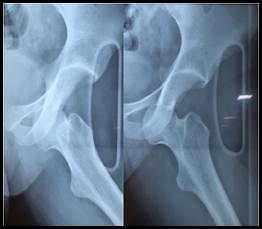

En el balance lesional primario no se constataron lesiones de órganos nobles, en tanto que a nivel osteoarticular se destaca posición viciosa a nivel de miembro inferior izquierdo en rotación externa, abducción y flexión (Figura 1), sin alteraciones a nivel de piel ni de la esfera neurovascular. Valorado en primera instancia en puerta de emergencia del Hospital de Carmelo, las radiografías iniciales (Figura 2) evidencian una luxación anterior de cadera izquierda tipo obturatriz, por lo que es enviada al Centro Hospitalario Pereira Rossell para su resolución. Al momento de arribar con 10 horas de evolución y sin cambios clínicos, se procede a reducción cerrada de la cadera en block quirúrgico bajo anestesia general, traccionando en el eje de la deformidad con cierto grado de rotación interna, logrando reducción exitosa controlada bajo intensificador de imagen y estabilidad clínica en todos sus ejes de movimiento (Figura 3). Durante el postoperatorio inmediato, se constata indemnidad neurovascular del miembro y se realiza Tomografía Computada (TC) de la cadera afecta sin evidenciar trazos de fractura, fragmentos intraarticulares ni desplazamiento epifisario (Figura 4). Con buena evolución en sala, se otorga alta a domicilio con descarga del miembro afecto por 3 semanas y control en policlínica de ortopedia infantil en 1 mes.

Figura 3:  Radiografía post reducción